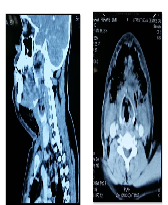

Gas Gangrene in the Neck Caused by an Odontogenic Infection- A Case Report